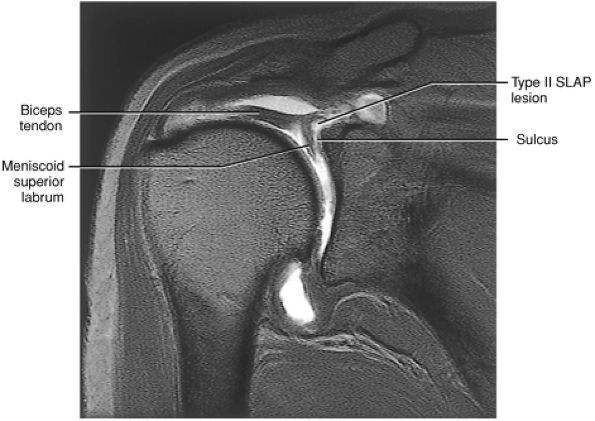

The SLAC lesion is combined with the anterior component of a SLAP 2 tear.

-

The SLAC lesion is a type of instability and not an impingement lesion.

![]() |

|

FIGURE 8.178 ● Potential sites of involvement in microinstability, including the anterior supraspinatus and anterior component of a SLAP 2 in the SLAC lesion; the posterior cuff and posterior component of a SLAP 2 in the posterior peel-back lesion; the classic anterior-to-posterior SLAP 2 lesion; anterosuperior impingement (ASI) involving the superior subscapularis, CHL–SGHL complex, the anterior supraspinatus and anterosuperior labrum, and the middle glenohumeral ligament (MGL) in anterior laxity.